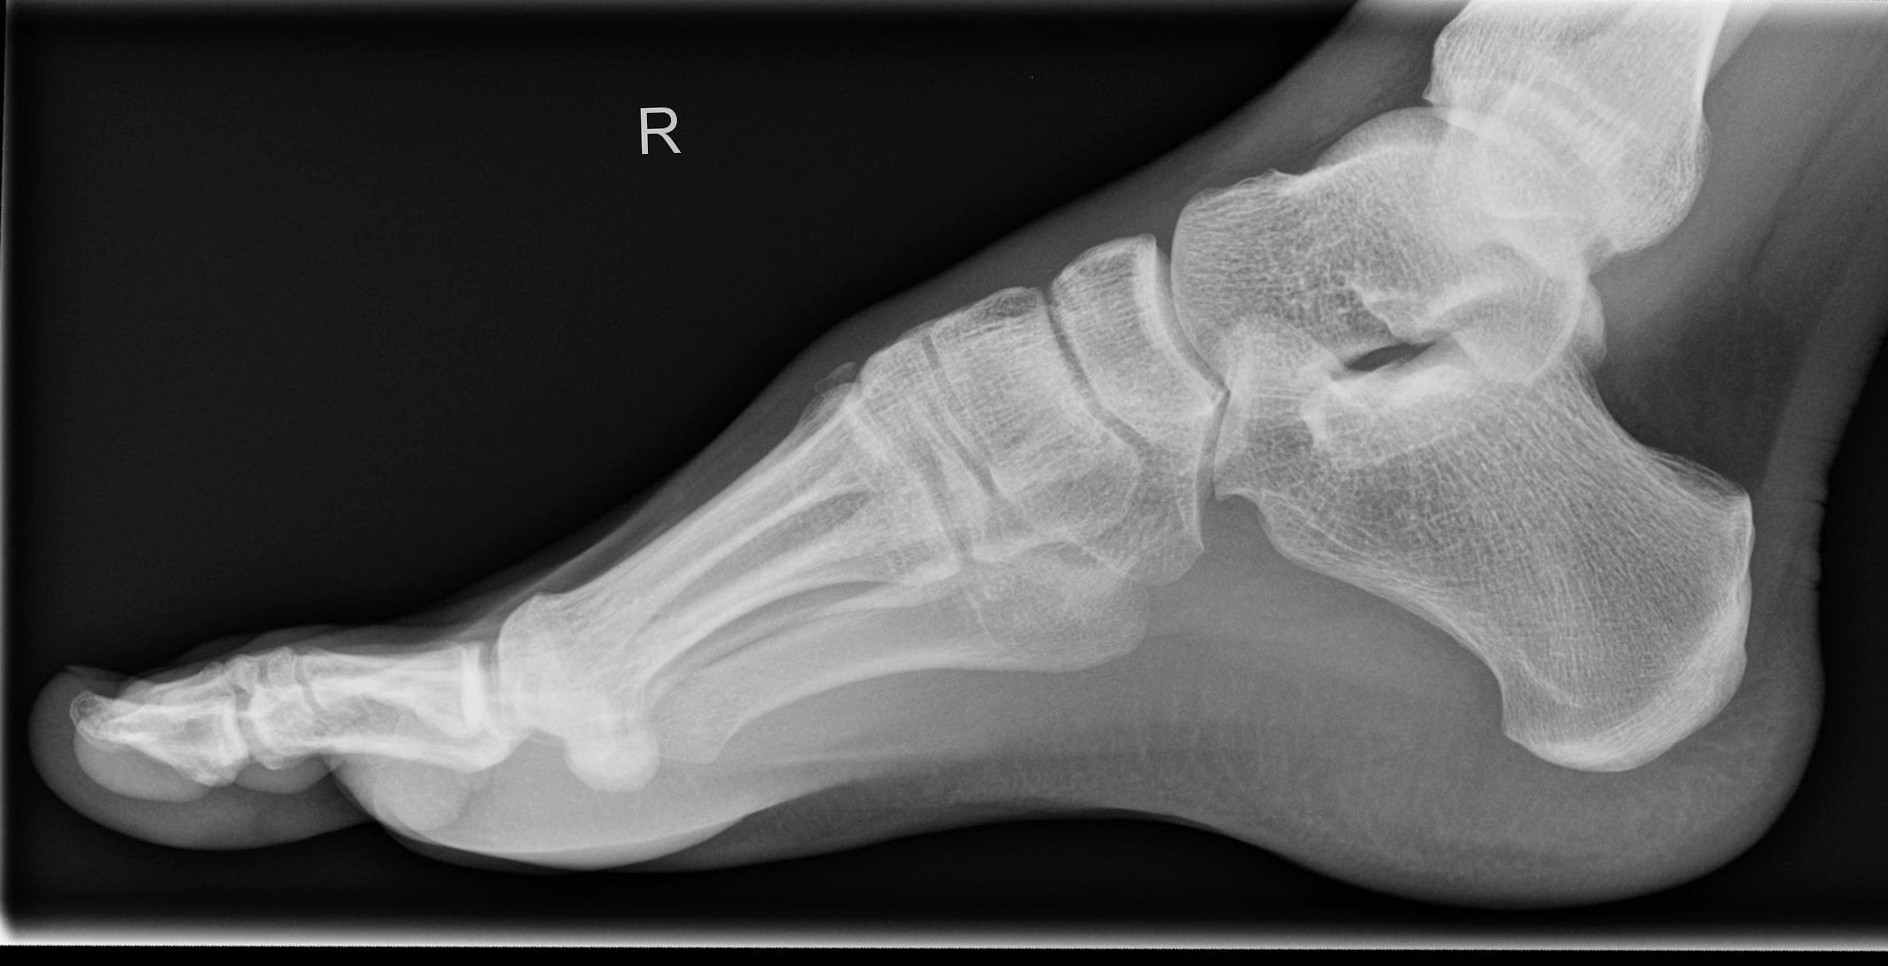

Fuß streng seitlich

Metatarsalien decken sich an ihrer Basis, bei Verdacht auf Senkfuß eine Aufnahme im Stehen mit Belastung, d.h. gesundes Bein anheben, mit angestelltem Bildempfänger und horizontalem Strahlengang.

Gut einsehbares oberes und unteres Sprunggelenk. Die Basen der Mittelfußknochen überlagern sich.